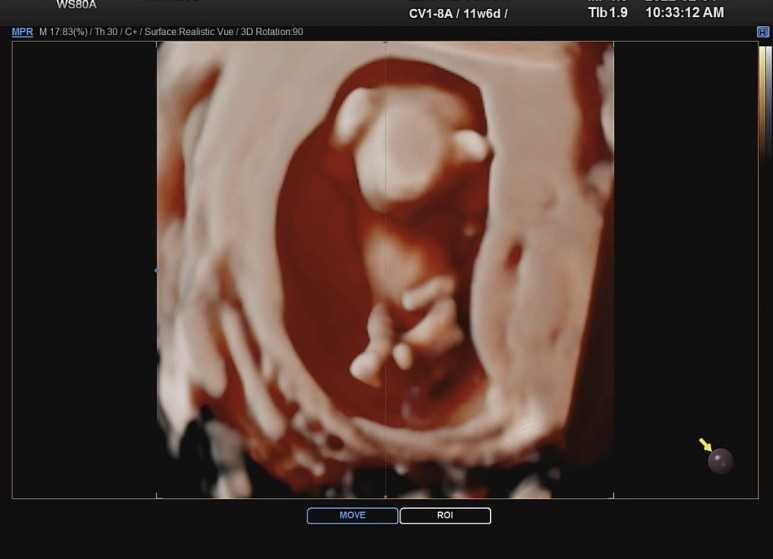

그리고 이 날 처음으로 입체초음파를..!!

머리에 양손 올리고 있는거 넘 귀엽 ㅜㅜㅜ 크흡 ㅜㅜ 남편이랑 나랑 진짜 심쿵해버렸다.

가느다란 다리 쭉 뻗고 있는거 뭐야뭐야.. 으아아아 배꼽에 탯줄 연결되어있는거 뭐냐구 ㅜㅜㅜ

아직 몸통보다 머리가 더 큰것도 진짜 심쿵포인트가 한두가지가 아니다.